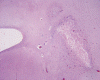

·         Histologically, PVL occurs as a well demarcated, small, irregular lesion, sometime with cavity formation, in the white matter at a short distance from the ventricle. The affected brain tissue is often mineralized and gives the chalky appearance. Although these chalky spots are very helpful in identification of PVL on gross examination, they can be very subtle and minute and requires careful examination for recognition.

Click on this icon to see a low magnification photo. The lesion is highlighted by the arrow.

Click on this icon to see the necrotic core and rimming reactive change.

Click on this icon to see the mineralized cells, likely a neuron, highlighted by an arrow. It is these mineralized cells that give the chalky spots.